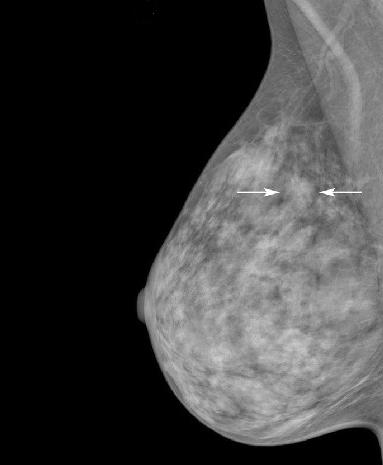

A mammogram with arrows indicating an asymmetry in the upper area of the breast.

A mammogram with arrows pointing to an asymmetry that was found to be an invasive ductal carcinoma.

Credit: BMC Med Imaging. January 2019. https://doi.org/10.1186/s12880-018-0303-3.